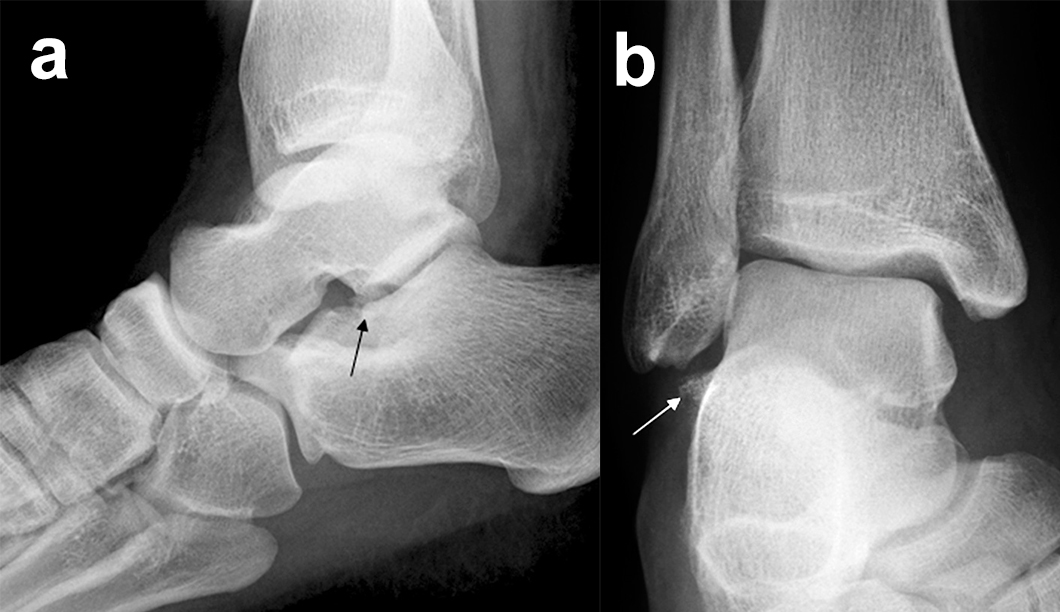

Prinzipiell werden konventionelle Röntgenaufnahmen vom OSG in 2 Ebenen (a.p. in 20° Innenrotation, „Mortise View“, und lateral) angefertigt (Abb. 1a, b). Zusätzlich können spezielle Projektionen wie die Canale oder Brodén-Aufnahme hilfreich sein, wurden in der klinischen Routine aber durch das CT oder DVT weitgehend verdrängt.

Bei in den konventionellen Aufnahmen nicht sicher auszuschließender Talusfraktur bzw. zur genauen Darstellung der Dislokation bei Taluskorpus- oder Talushalsfraktur sollte die Indikation zur CT-Diagnostik großzügig gestellt werden (Abb. 1 c, d). Insbesondere dient die CT-Diagnostik zur genauen Evaluierung der Frakturmorphologie und OP-Planung sowie auch zur Vermeidung möglicher übersehener peripherer Talusfrakturen 4.

Frakturen des Proc. fibularis tali

Frakturen des Proc. fibularis tali werden im konventionellen Röntgenbild nicht selten übersehen. Sie entstehen häufig nach schweren Distorsionen bzw. im Rahmen subtalarer Luxationen. Eine CT-Kontrolle nach geschlossener Reposition subtalarer Luxationen ist daher obligat (Ab. 15). Der Proc. fibularis tali ist über den anterolateralen Zugang oder schräg verlaufenden Ducroquet-Ollier-Zugang gut zu erreichen. Die subtalare Arthroskopie über anterolaterale und posterolaterale Portale bietet wie bei intraartikulären Kalkaneusfrakturen die Möglichkeit der exakten Kontrolle der geschlossenen Reposition bei einfachen Frakturformen 35. Nach anatomischer Reposition und temporärer Fixierung mittels 1,0 Kirschnerdraht erfolgt die Osteosynthese mittels Kleinfragmentschrauben (2,7 bzw. 3,5 mm), die unterhalb der Knorpel- Knochengrenze eingebracht werden und für eine ausreichende Stabilität sorgen (Abb. 16). Kleinere, nicht anatomisch refixierbare Fragmente, oder Fragmente mit starker Knorpelkontusion werden vorzugsweise exzidiert (Abb. 17). Gleiches gilt für Frakturen des Proc. posterior tali zur Vermeidung einer posttraumatischen Arthrose 23736.